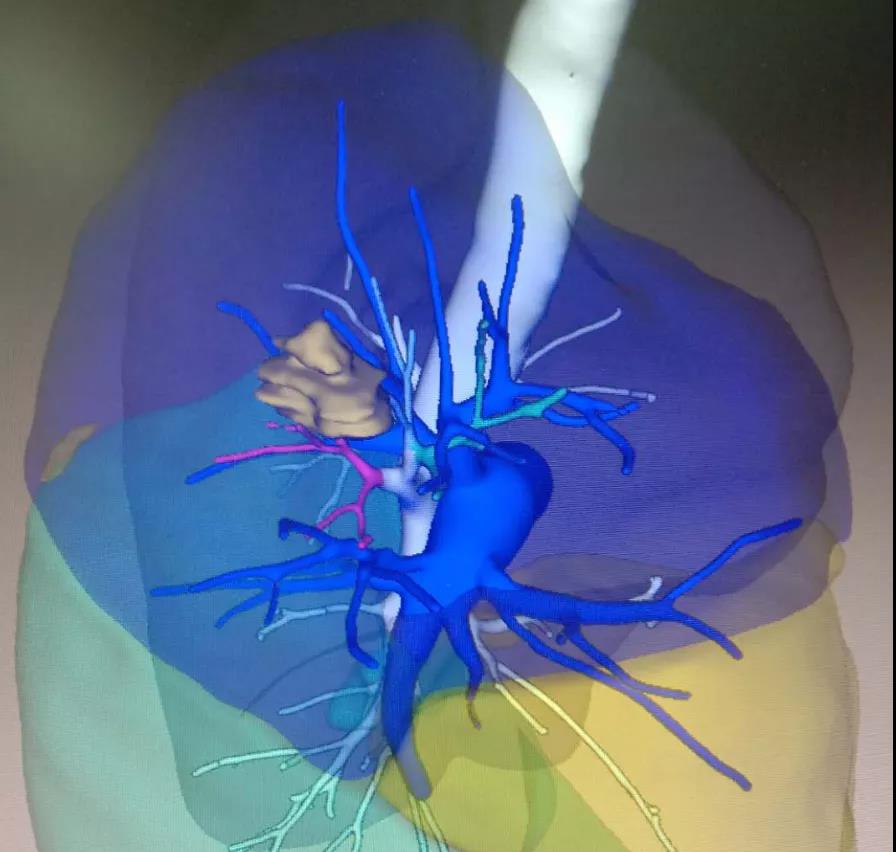

没想到我这么大岁数,切掉一个肺叶的十年后,再次做这么复杂的手术还这么顺利。 D大爷今年72岁,10年前曾行左肺上叶切除+淋巴结清扫术,手术标本病理为腺癌,术后给予了四次化疗。当时的胸部CT即可见右肺上叶小结节影,术后定期复查,病灶缓慢增大,一度略有缩小,此后再次逐渐增大。结合患者一直随访的影像学资料,杨如松院长考虑为右上肺新发恶性肿瘤。 2015年胸部CT 2020年胸部CT 虽然患者及其家属手术的意愿非常强烈,但此手术难度较高,原因在于: 1.患者年龄较高,手术风险大。 2.患者10 年前肺癌手术切除左边肺的一半,肺功能丧失较多。 3.病灶在右上肺的深部,切除有一定的难度。 为了保证患者术后的生活质量,我们不能够做肺的楔形切除这样的简单肺手术,而需要行肺段的切除。 EDDA重建提示病灶位置深 如果放在以前该患者就只能做做放化疗等保守治疗了。幸亏南京胸科医院目前引进了各种国内乃至国际上的先进技术。 如EDDA术前三D成像技术;只有单一3cm长切口的单孔胸腔镜技术;近红外荧光镜肺段、亚肺段精准定位技术等。 有了这些技术,杨如松院长心中有了底气。杨院长根据病人的情况设计手术方案,尽量减轻手术创伤,让接受第二次肺部复杂手术的高龄病人能够耐受,并且在术后能够顺利恢复。 根据术前EDDA三维重建,患者进行了单孔荧光胸腔镜S1a+2a切除术,术中先用ICG反染法确定段间面,再用膨胀萎陷法印证段间面,这保证了手术切除的精准性。 患者术中快速病理为贴壁型腺癌,这也印证了杨如松院长术前对患者肺结节良恶性的判断。 术后5天,D大爷非常顺利的出院了。出院前开心的窦大爷连声感谢杨如松院长:没想到我这么大岁数,切掉一个肺叶的十年后,再次做这么复杂的手术还这么顺利,谢谢、谢谢! 基本情况

手术方案